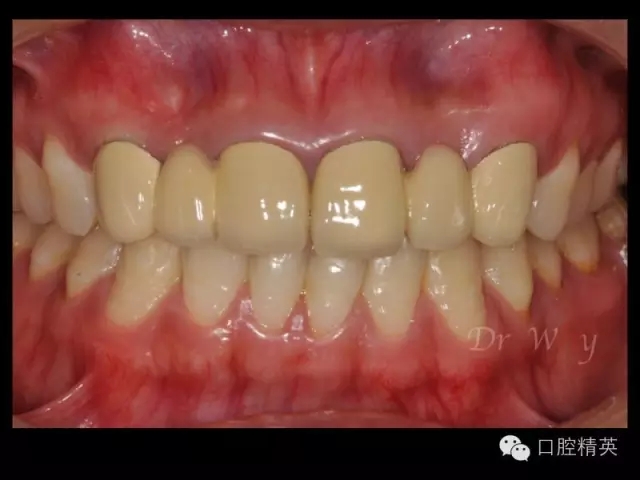

圖片11修復(fù)體完成像

圖片12修復(fù)前后對(duì)比口內(nèi)像